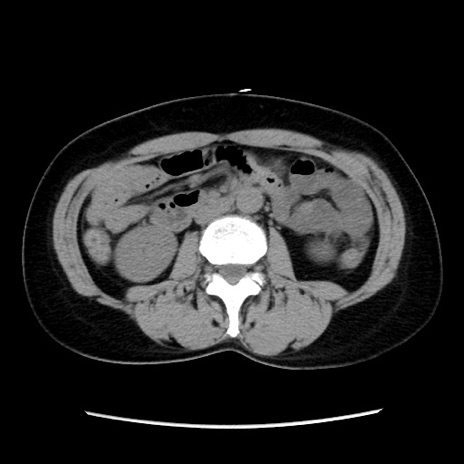

症例10(横断像)

【症例】 50歳代女性

【主訴】 腹痛

【現病歴】前日生レバーを食べた。今朝に排便あり。 昼前に突然発症の腹痛を生じ、当院救急外来を受診した。

【身体所見】 意識清明、腹部:平坦、軟、下腹部やや左を中心に圧痛・反跳痛あり、筋性防御あり